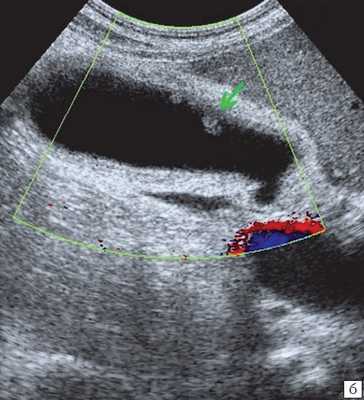

При распространенном холестерозе визуализируются множественные гиперэхогенные образования, дающие картину "земляничного" желчного пузыря (рис. 3).

![Эхограмма - множественные полипы в желчном пузыре, картина земляничного желчного пузыря]()

а) Множественные полипы в желчном пузыре, картина "земляничного" желчного пузыря.

![УЗ-картина полипов в желчном пузыре - режим ЦДК, кровоток не регистрируется]()

б) В режиме цветного допплеровского картирования кровоток не регистрируется.